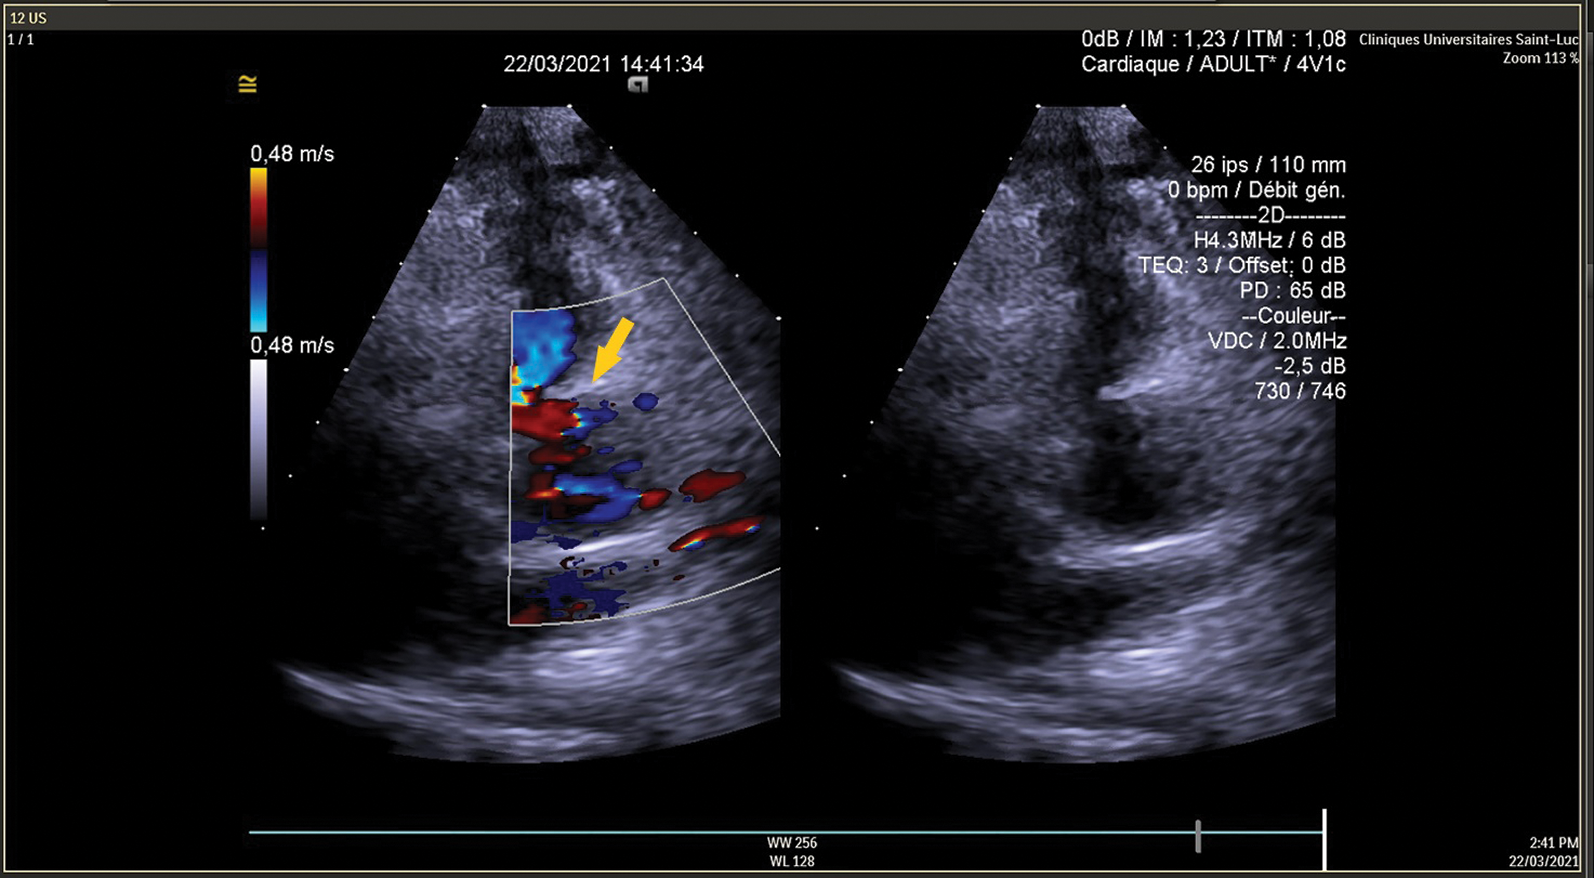

CPB weaning was easy with normal EKG, TEE showed good LV function with antegrade flow in the proximal LAD (Figs. 7 and 8). Postoperative course was uneventful, the patient was discharge on the 6th postoperative day.

Figure 8: TEE shows antegrade flow in LAD